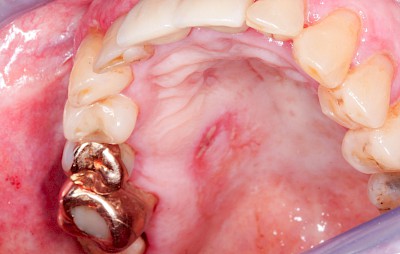

Orale lichenoide Läsionen (OLL) sind häufig im Nahbereich von Amalgamfüllungen oder von metallischem Zahnersatz zu beobachten. In diesen Fällen sollte ein Zahnarzt hinzugezogen werden, wobei der Austausch der Restauration sehr kritisch abzuwägen ist.

Metalltätowierung

Häufig zu beobachten sind einzelne dunkle Flecken im Nahbereich der Zähne. Häufig handelt es sich dabei um Amalgam- oder Metall-Tätowierungen. Bei zahnärztlichen Behandlungen kann es zur "Versprengung" von Metall-Anteilen von Füllungen oder Kronen kommen. Diese lagern sich dann reizlos in die Schleimhaut ein.